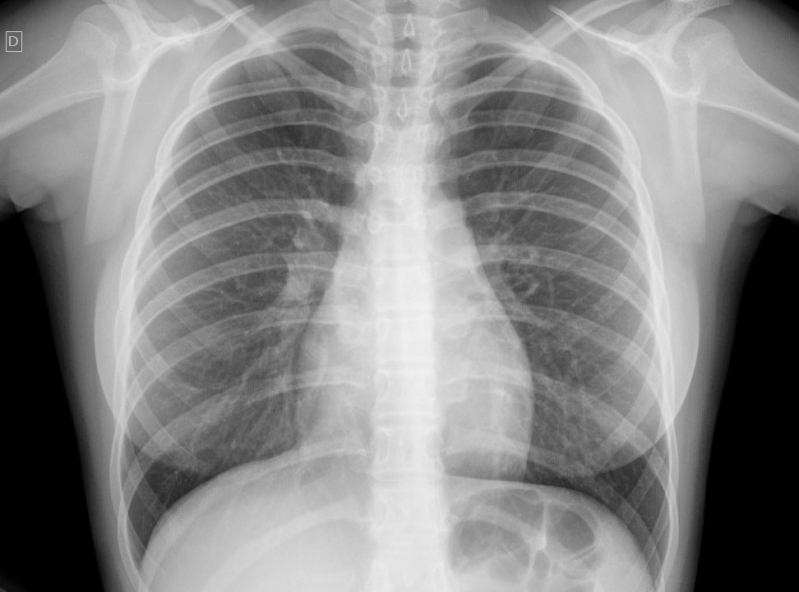

Impressora para Raio-x

RS IMPRESSORASUma impressora para raio-x deve ser específica para que haja o perfeito resultado, principalmente, se houver algum incoveniente que necessita de tratamento. Esse tipo de equipamento é...

Uma impressora para raio-x deve ser específica para que haja o perfeito resultado, principalmente, se houver algum incoveniente que necessita de tratamento. Esse tipo de equipamento é imprescindível em hospitais e clínicas.

Para uma peça de excelência, é de extrema autoridade contar com a ajuda de profissionais especializados e aptos a expandir um serviço de particularidade.

Deseja mais informações sobre impressora para raio-x?

Desenvolvendo um trabalho que oferece comodidade e certificando soluções inovadoras em outsourcing de impressão, a RS Impressoras é consolidada em seu segmento por conta da excelência apresentada em seus serviços.

Priorizando sempre as necessidades dos seus clientes, a empresa conta com uma equipe de profissionais elevadamente qualificados e aptos a expandir um serviço completo e de extrema particularidade.

Com experiencia a começar de 2007, a RS Impressoras garante a satisfação dos seus solicitantes, procurando sempre melhorias em cada um dos seus processos. Saiba mais entrando agora mesmo em contato!

Uma impressora para raio-x deve ser específica para que haja o perfeito resultado, principalmente, se houver algum obstáculo que necessita de tratamento. Esse tipo de equipamento é imprescindível em hospitais e clínicas.

Para uma peça de excelência, é de extrema seriedade contar com a ajuda de profissionais especializados e aptos a ampliar um serviço de particularidade.

Deseja mais informações sobre impressora para raio-x?

Desenvolvendo um trabalho que oferece comodidade e certificando soluções inovadoras em outsourcing de impressão, a RS Impressoras é consolidada em seu segmento por conta da excelência apresentada em seus serviços.

Priorizando sempre as necessidades dos seus clientes, a empresa conta com uma equipe de profissionais elevadamente qualificados e aptos a ampliar um serviço completo e de extrema particularidade.

Com experiencia doravante 2007, a RS Impressoras garante a satisfação dos seus solicitantes, procurando sempre melhorias em cada um dos seus processos. Saiba mais entrando agora mesmo em contato!